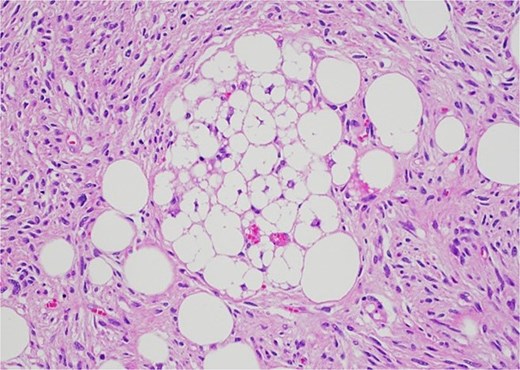

Histology revealed a multilobulated spindle cell lesion, with low- and high-grade areas, with an abrupt transition between these areas. There was an adjacent focus of adipose tissue with rare cytologic atypia suggestive of possible WDL, which indicated that the tumor mass may represent DDL. However, there was a single focus of lipoblasts identified, bringing up the differential of pleomorphic liposarcoma. Therefore, in situ hybridisation was performed and showed MDM2 amplification, which confirmed the diagnosis of DDL, with likely homologous lipoblastic morphology. The tumour was excised with clear margins (Figs 3–8).

Low-grade component with abrupt transition to high-grade component (asterisk).